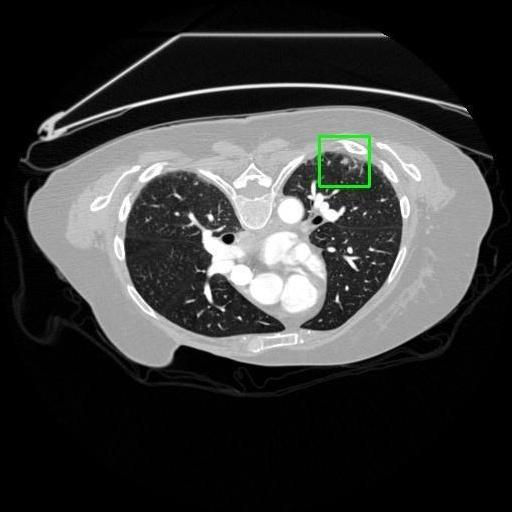

We developed an AI-based system using deep learning models for analyzing lung CT scans to detect and classify pulmonary nodules. We chose the YOLOv11 architecture for its enhanced object detection capability and adapted it specifically for medical imaging, incorporating pixel-level precision and severity classification.

Classification into three severity levels with colored bounding boxes.

Successfully built and deployed an AI model (YOLOv11) capable of detecting lung nodules in CT scans with high accuracy and real-time performance.

Designed a severity classification system that categorizes nodules into null, moderate, and severe using colored bounding boxes, assisting in rapid clinical decision-making.